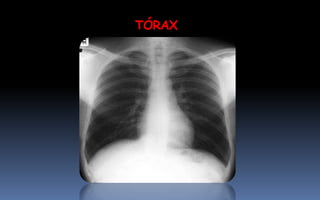

TÓRAX

1. PAR RADIOLOGICO

2. CENTRADO

3. PENETRADO

4. INSPIRADO

Rx de tórax simple o convencional